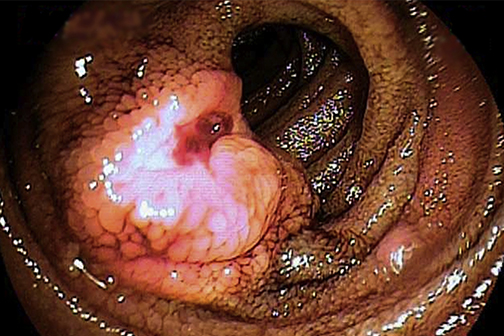

A team of physicians at LSU Health New Orleans has found that endoscopy combined with the administration of antiplatelet or anticoagulant agents is a safe and effective technique for identifying hidden sources of gastrointestinal bleeding. The work is published online in Gastrointestinal Endoscopy (GIE) and reviewed in New England Journal of Medicine Journal Watch in October 2016.

The LSU Health New Orleans team developed a novel technique to find the leak --giving these patients blood thinners to stimulate or provoke bleeding before endoscopy because some sources are only visible when actively bleeding.